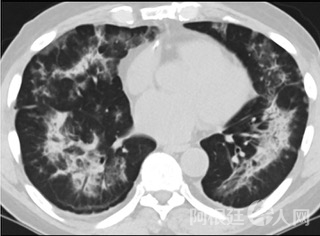

疑点二,中国科研工作者从60篇研究论文中筛选出142位电子烟肺炎患者的250张影像图片,邀请3位放射科权威专家,对上述全部影像图片、相关病人临床信息以及文献原文进行了仔细全面研究与审查,又有了新的发现。

6天后的轴向CT平扫图像显示毛玻璃影变为实变和轻度结构扭曲。(同一病人CT影像)

16位被文献报道为电子烟肺炎的患者被专家判定为“病毒性感染”,即有可能是新冠肺炎的“疑诊患者”,其中更有5位临床症状和治疗情况相对完整的患者被判定为“中度可疑”。因此在2019年美国报道的电子烟肺炎中存在病毒性感染的病例,而且不排除美国电子烟肺炎中存在新冠肺炎的可能性。